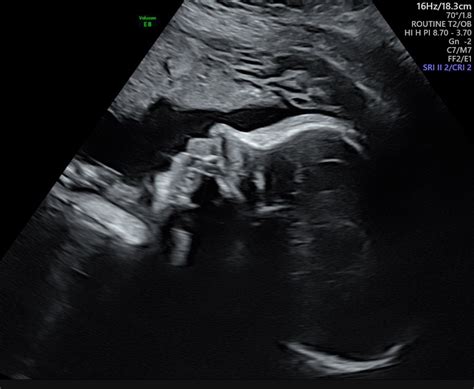

The primary destination of a growth scan is not just to see the babe, but to gather measurable data to ensure they are germinate at an appropriate rate. Obstetricians use these scan to supervise fetal health and observe any potential complication that might require closer observance or former intervention. During the exam, a sonographer will quantify specific parts of the baby's body to gauge their sizing and cheque for ontogenesis trends.

Once the scan is complete, you will receive a report containing assorted numbers and, ofttimes, a graph shew percentile lines. It is common for parents to feel overwhelmed by these statistics, especially when they hear terms like "percentile" or "small for gestational age". However, it is crucial to recollect that infant, just like adult, come in all shapes and sizes.

- development scan images